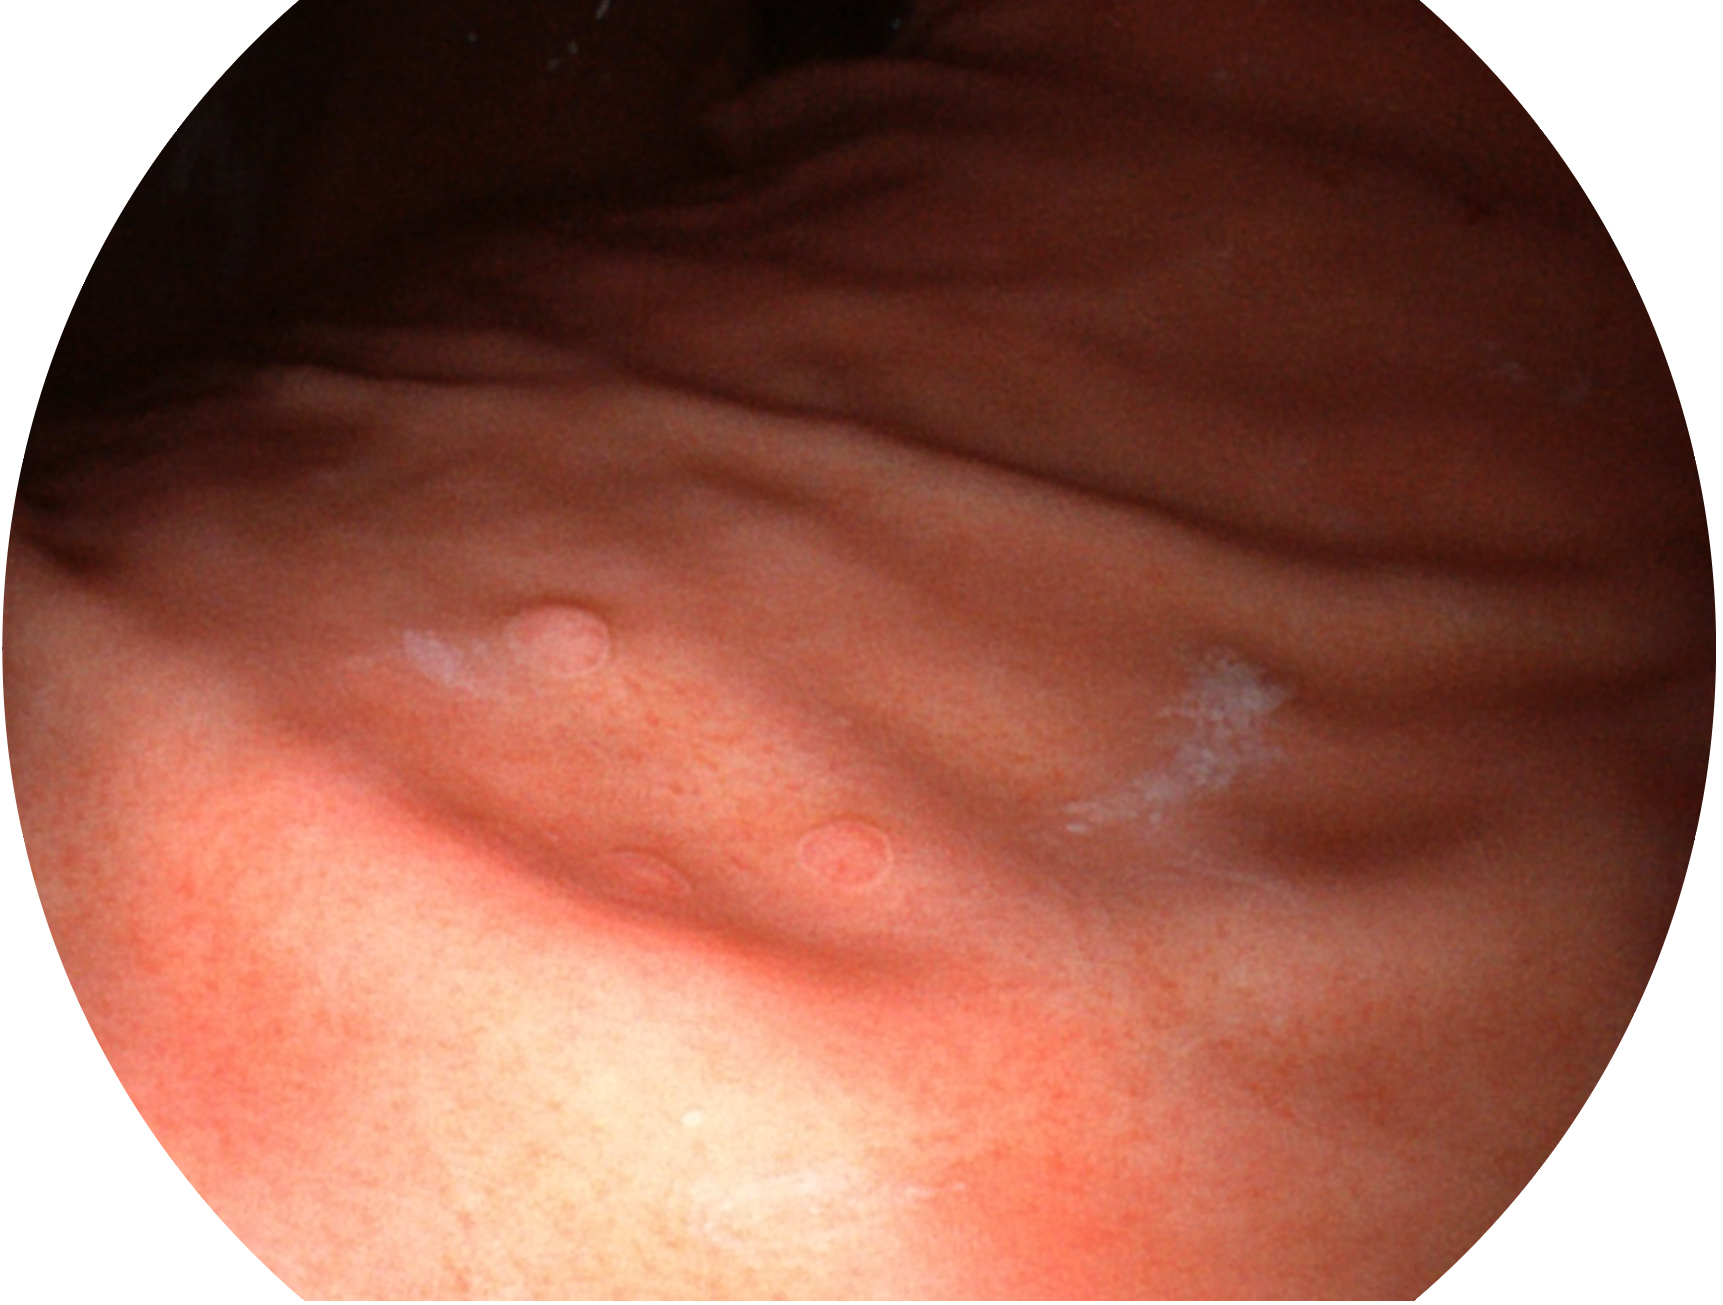

1xBET新开发的内镜染色技术,主要是基于多波长LED 光源的开发,VLS-55Q 四波长LED 光源是由四个不同颜色的LED光按照相应照明模式所规定的特定发光比例进行合束后形成,合束后形成的照明光的光谱由红光、绿光、蓝光及蓝紫光这四个不同的波段范围构成。具有更高光谱自由度,通过光谱比例的控制,实现了聚谱成像技术,英文全称为“Spectral Focused Imaging, SFI”,缩写为“SFI”和光电复合染色成像技术,英文全称为“Versatile Intelligent Staining Technology, VIST”,缩写为“VIST”。